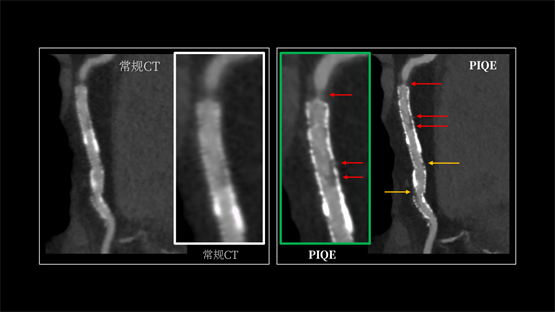

INSIGHT Pioneer 利用PIQE技术,首次实现了“16cm 宽覆盖 +超高分辨率”在同一CT系统上兼得。它能显著锐化支架轮廓,有效抑制金属伪影与硬化伪影。即便在多枚支架重叠、支架内径细小、严重钙化或心率波动的复杂病例中,依然能清晰显示支架内腔通畅情况及贴壁斑块性质。这意味着,医生在手术规划、介入治疗和术后随访中,都能更可靠地依赖CT来确认结构变化。日本仙台厚生医院心血管内科主任医师Shitaro Honda在实际应用中反馈:“PIQE使直径2.25mm的细小支架也能清晰呈现,能更清晰地显示血管。”

(左图为常规图像,右图为应用PIQE技术后的超高清图像)